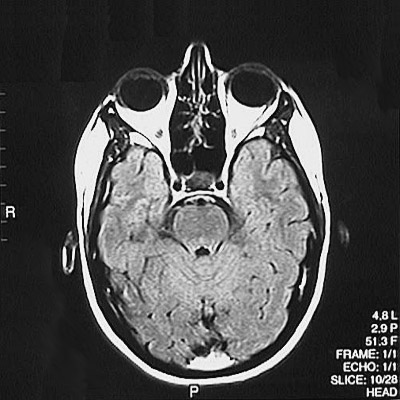

This is a normal axial FLAIR MRI scan demonstrating the temporal lobe and occipital lobe and basilar artery and internal carotid artery and basis pontis and aqueduct of Sylvius and cerebellar vermis and ethmoid sinus and pituitary and globe of eye and lens of eye.